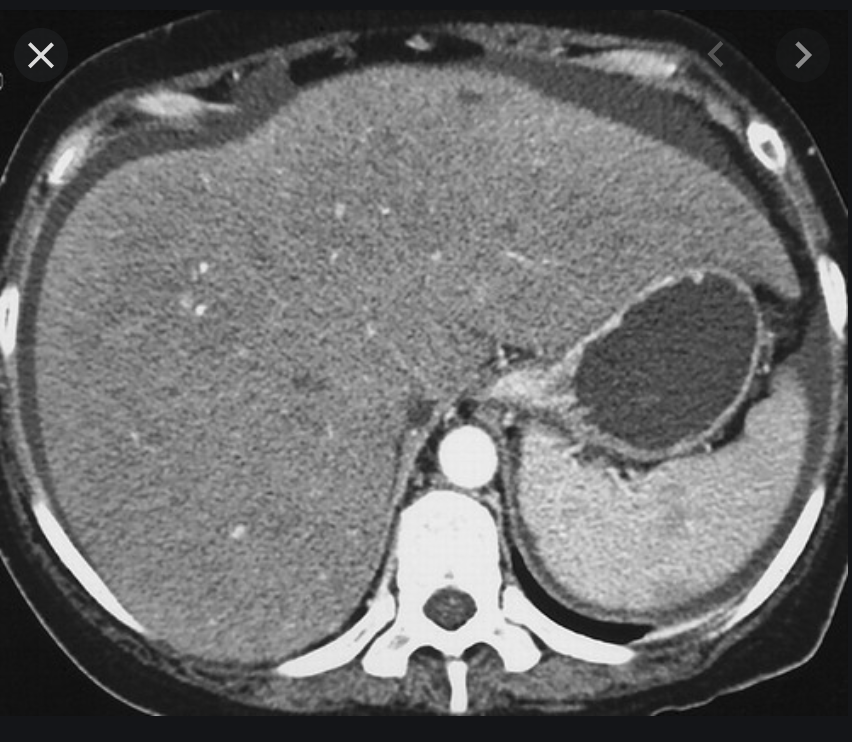

Normal liver attenuation

Ix: NCCT normal app of liver relative to spleen; HUs.

Ix: liver should be slightly hyperattenuating relative to spleen; normal liver 10HU < spleen.